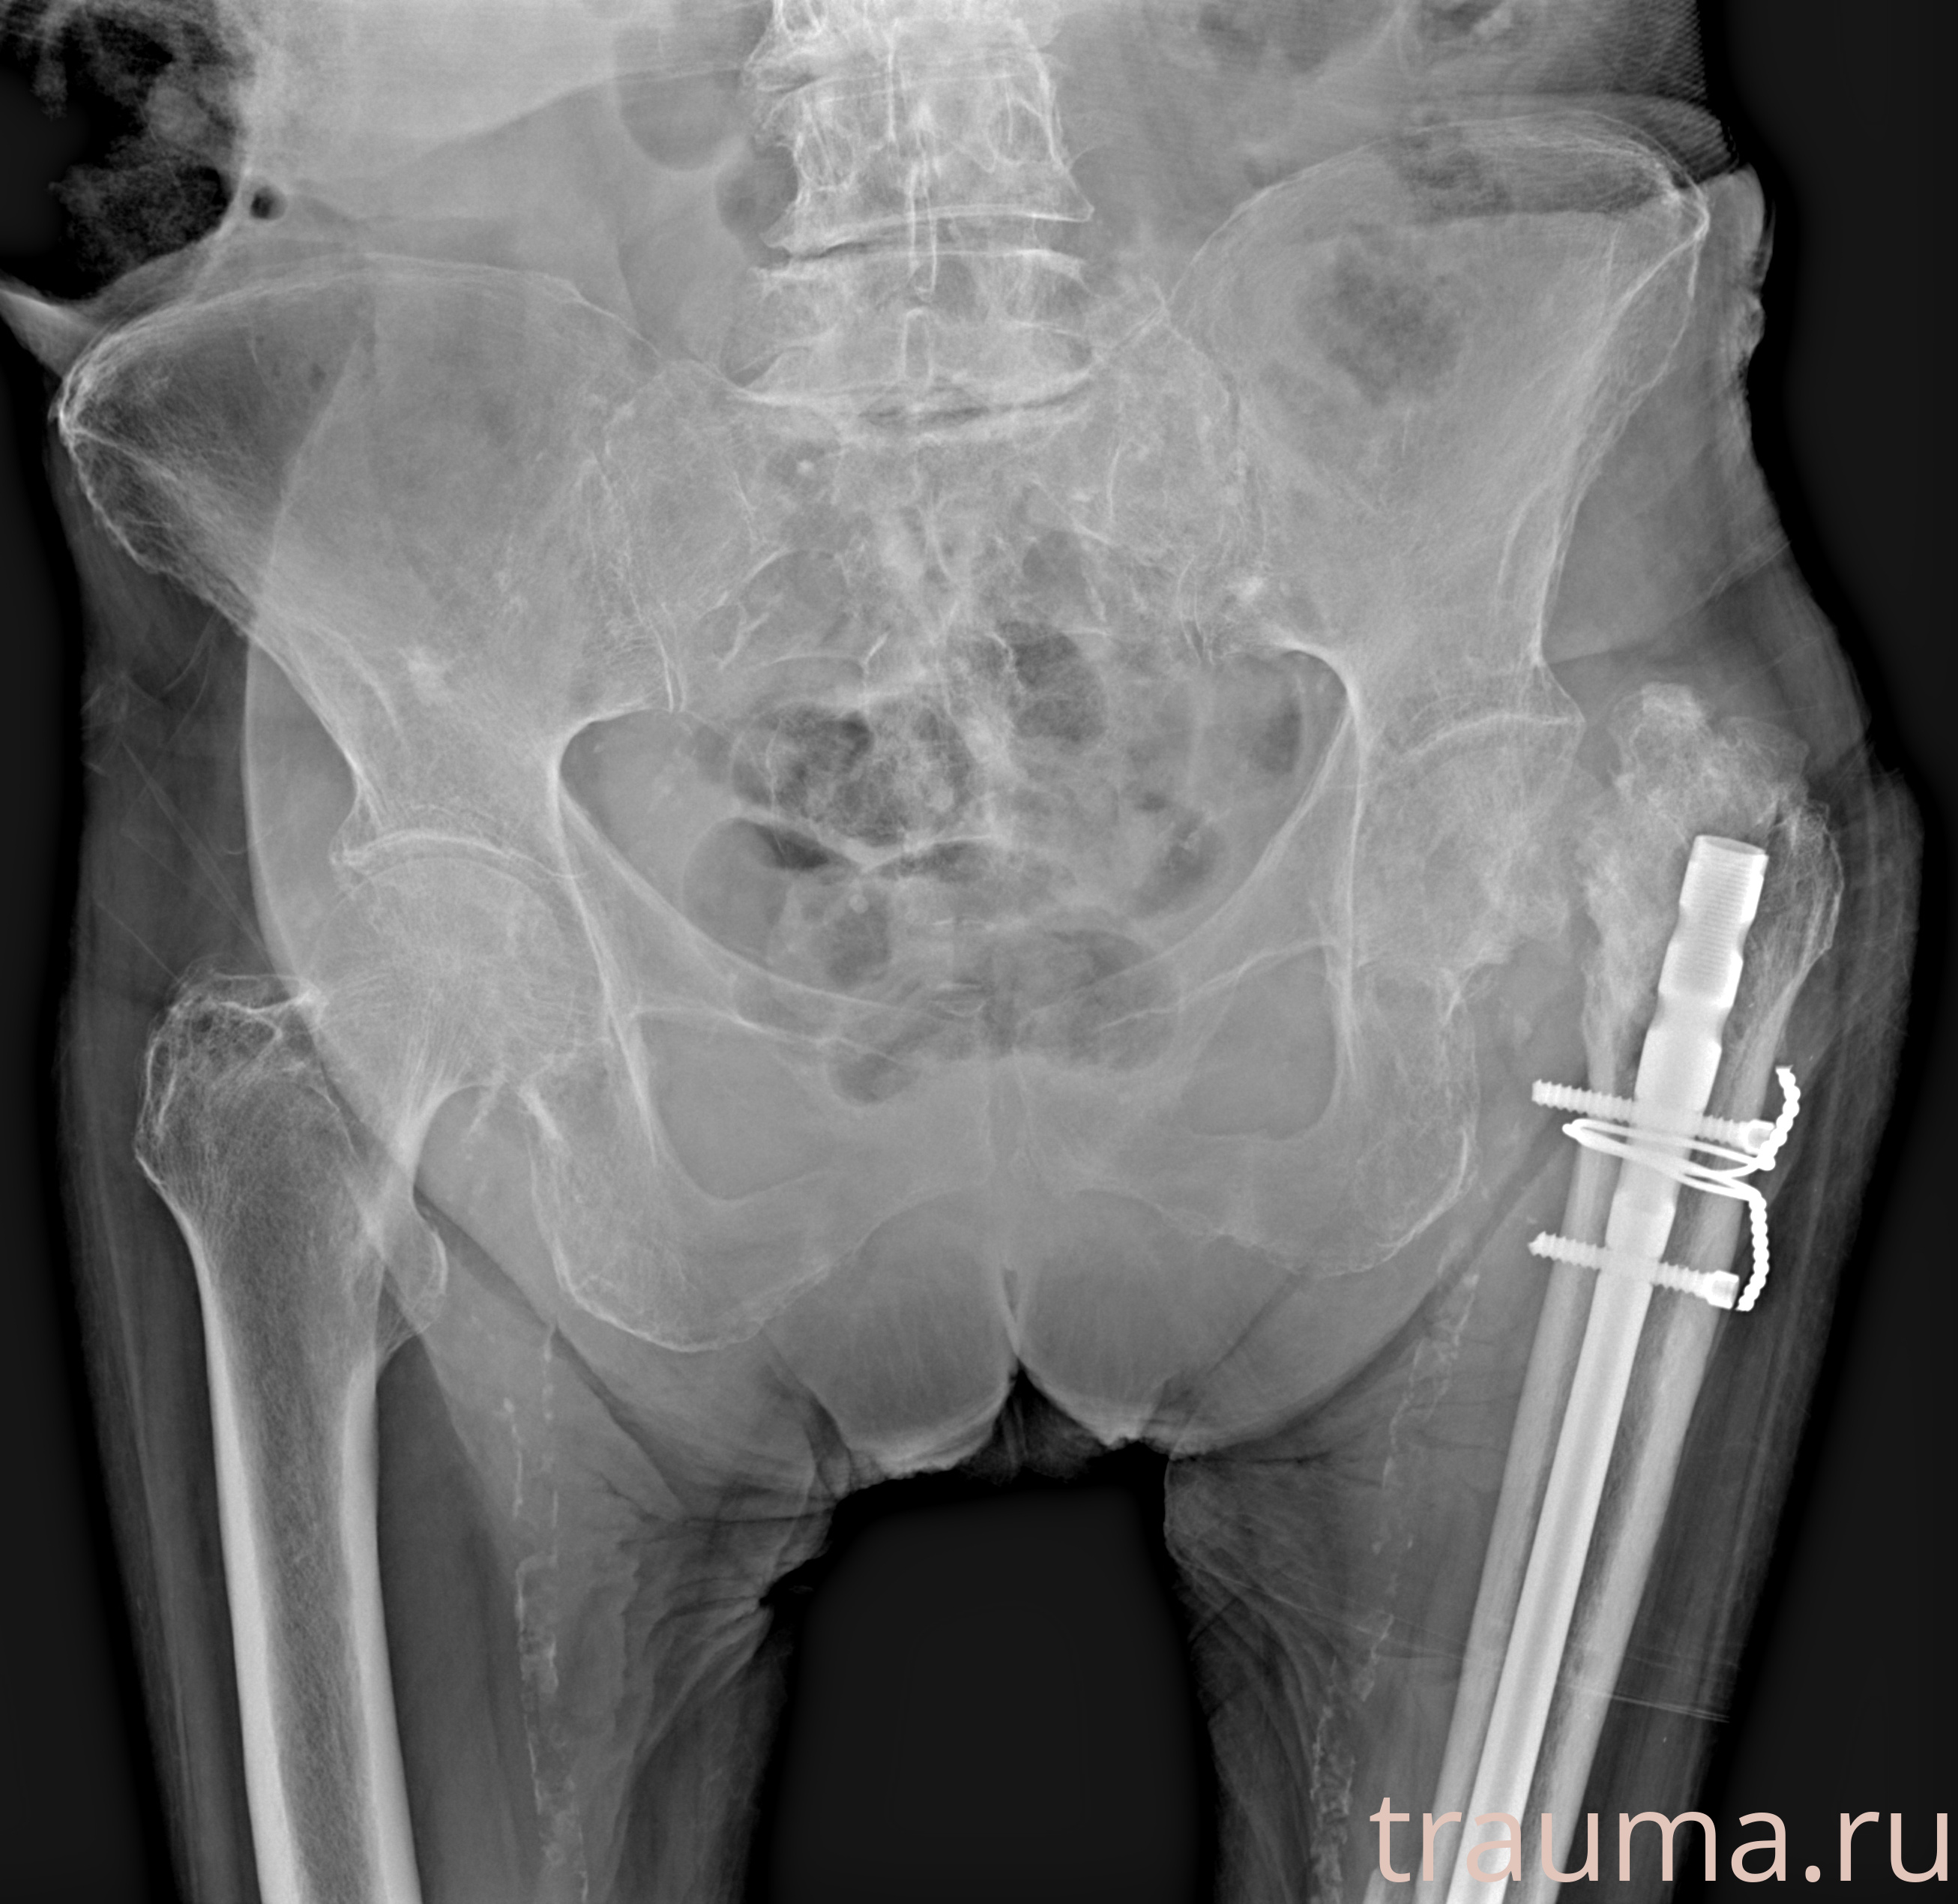

Рентгенограммы

Рентген на дому: по вашему адресу приезжает врач-рентгенолог, травматолог-ортопед с мобильным рентгеновским аппаратом, проводит диагностику травмы или заболевания, делает необходимые рентгенограммы, дает рекомендации по дальнейшему лечению. Получить качественные снимки в домашних условиях возможно благодаря уникальной методике, разработанной МосРентген Центром для института  Склифосовского